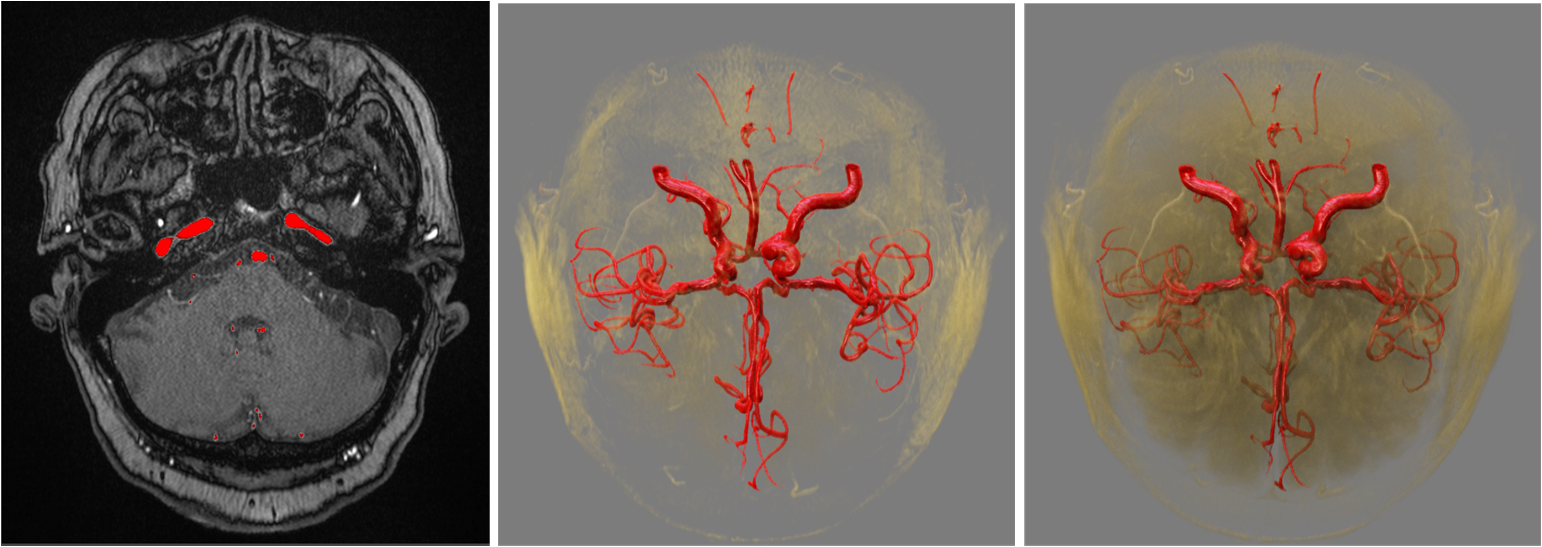

Semantic segmentation techniques are used to extract features of lesions or regions of interest and assign different material properties to them in rendering.

3D visualization of cerebral vessels

Visualization without segmentation & Visualization with segmentation